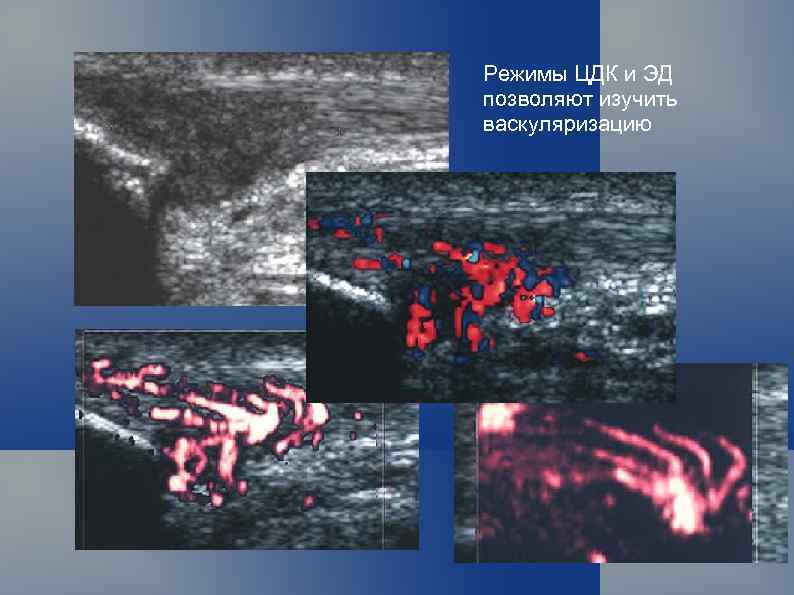

Режимы ЦДК и ЭД позволяют изучить васкуляризацию